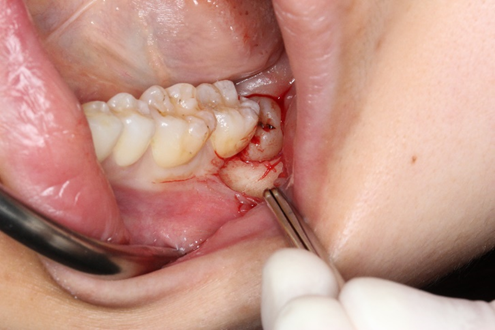

左側下顎7番部分を縦に切開します。

切開が完了したら、骨からはがすように歯肉をめくります。

歯肉をめくると、横向いた親知らずの歯冠部分が目視できるようになります。

歯冠分割です。

歯は、歯冠方向の1方向にしか抜けてこないため、歯冠部分を削り分割します。

歯冠部分の分割、除去が完了しました。